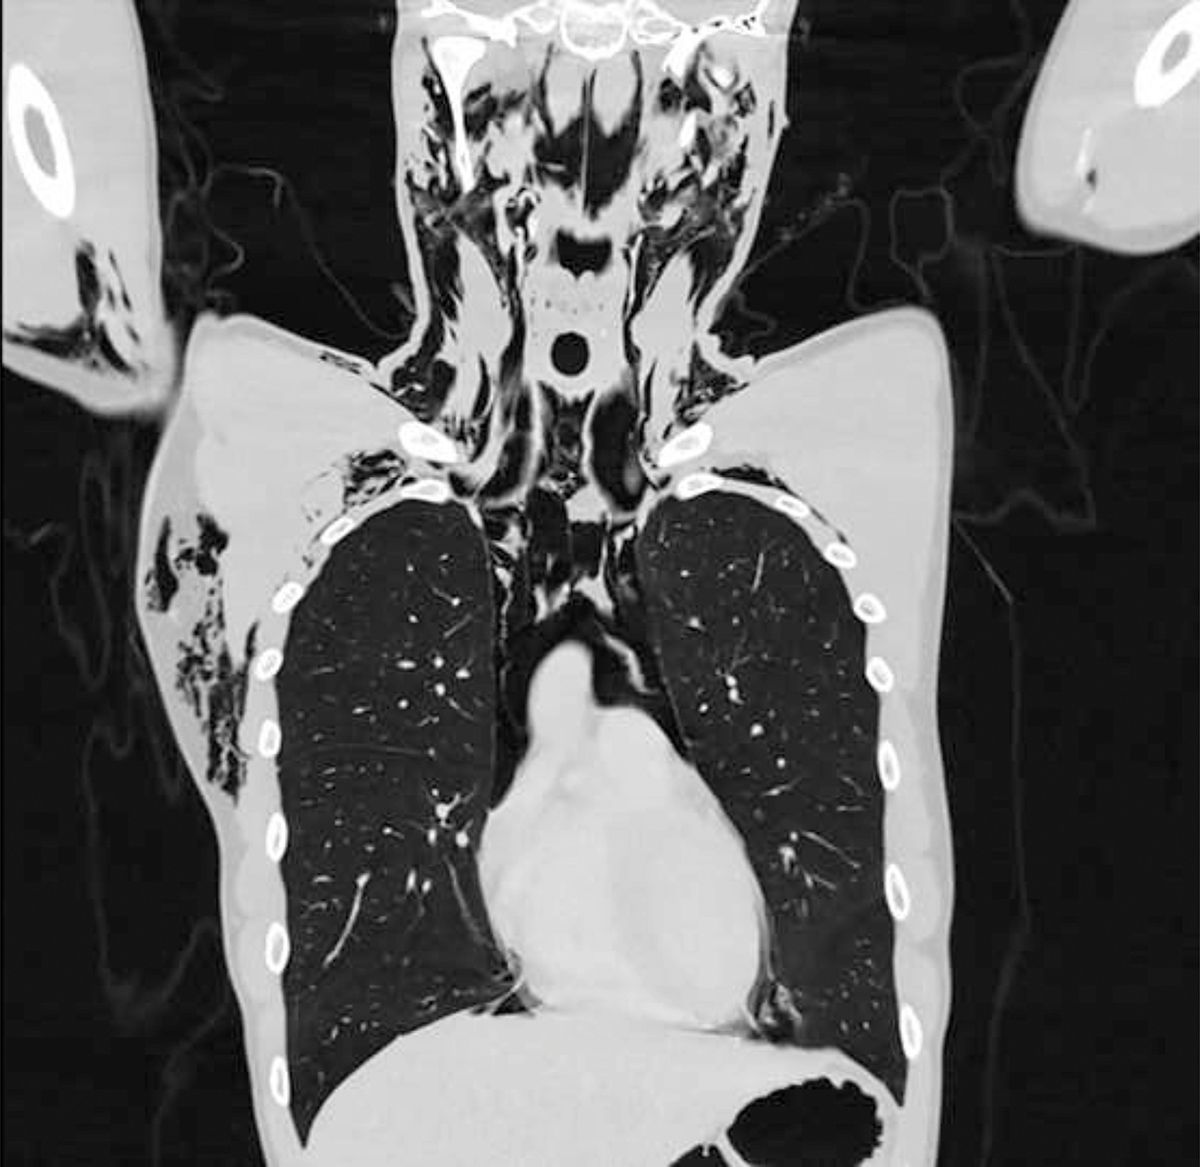

Even een kleine waarschuwing van onze kant, omdat wij weten dat jouw sokken niet zo stijf zijn geworden door deze dagelijks in behangplaksel te dopen. Maar een 20-jarige Zwitserse man heeft ernstige longproblemen opgelopen, omdat hij iets te fel de hand aan zichzelf sloeg. Met hevige pijn en kortademigheid moest hij met spoed naar het ziekenhuis. Na enkele röntgenfoto’s bleek de man een zogeheten spontaan pneumomediastinum te hebben opgelopen: er was lucht in de holte tussen zijn longen terecht gekomen.

Op de röntgenfoto’s was een grote hoeveelheid lucht te zien die uit de longen van de man was ontsnapt. Foto: Science Direct